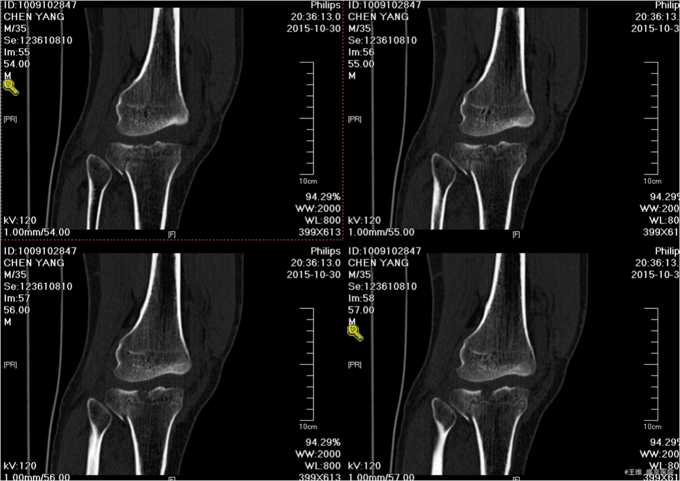

主诉:车祸致右膝部疼痛肿胀活动障碍5小时 现病史:患者及家属代述患者于2015年10月30日下午5点时在走路时被汽车撞伤发生车祸,导致右膝部疼痛肿胀活动障碍,当时无昏迷,送至沈阳中医4院,行DR及影像学检查示:右胫骨平台骨折,右12肋骨骨折。家属为行进一步治疗来我院就诊。经门诊检查后收入我科。患者病来,意识清醒,无头痛头晕,无咳嗽咳痰,无心慌气短,饮食正常,小便正常,大便未排,体重无变化。

专科查体:右小腿近端肿胀明显,无明显开放性创口,痛阳性,叩击痛阳性,可触及骨擦音骨擦感,压痛阳性,,右下肢感觉未见明显异常,右足趾感觉运动未见明显异常,双侧足背动脉搏动良好,末梢血运良好